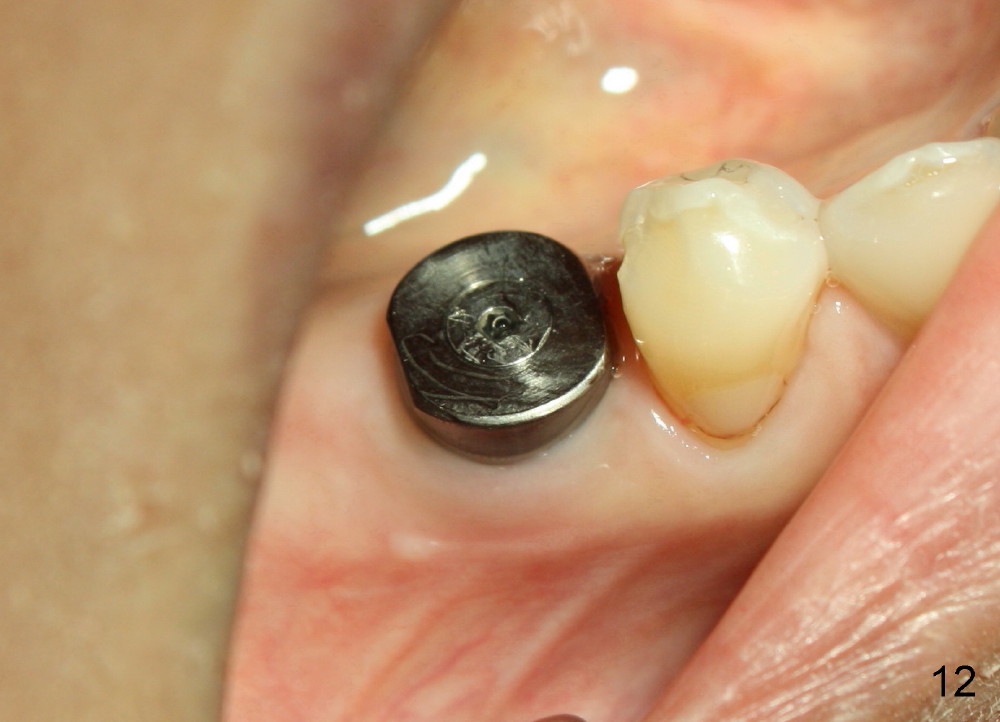

The implant appears to be osteointegrated 4 months postop (Fig.11). A healing cuff is inserted in preparation for restoration 2-4 weeks later (Fig.12). Fig.13 shows that the crown is just cemented. One month later, the patient is concerned about the metal showing through the gingiva (*). To overcome the issue, gold coated implant is used, an implant is placed more lingual (smaller), or bone graft is placed buccal to the implant. There is no bone loss 3 years 5 months post cementation (Fig.14).